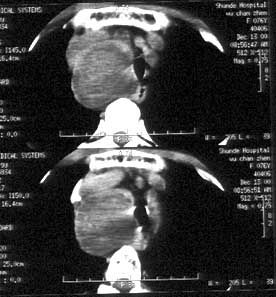

相關圖片

![]() | ![]() | ![]() |